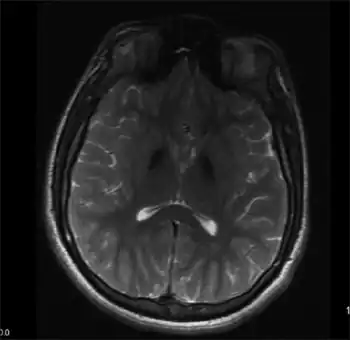

| Mitochondrial membrane protein-associated neurodegeneration-Symmetric, hypointense lesions in the globus pallidus, and substantia nigra | |

MPAN might be suspected with typical presentation and findings on MRI (Magnetic Resonance Imaging), these include evidence of iron deposition in the brain, particularly in the basal ganglia (globus pallidus and substantia nigra).[1][3] The diagnosis is confirmed by genetic testing identifying harmful variant(s) in C19orf12.[1]